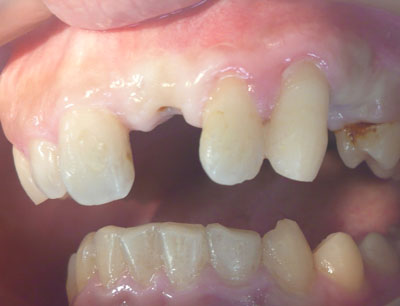

| Before | After |